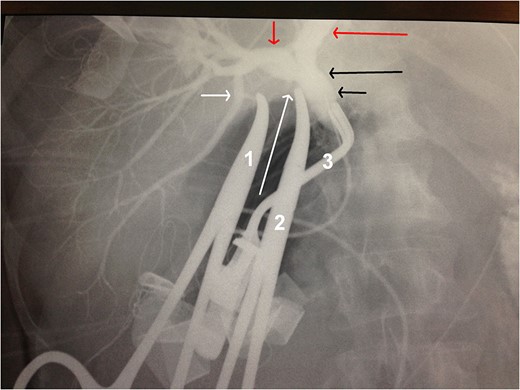

Intraoperative cholangiography. Short white arrow: the origin of the aberrant bile duct from the RPSD. Long white arrow: the stump of the cystic duct. Short red arrow: RHD. Long red arrow: LHD. Long black arrow: CHD. Short black arrow: CBD. Forceps 1 holds the stump of the aberrant bile duct. Forceps 2 holds the stump of the cystic duct. Forceps 3 blocks the CBD for the intraoperative cholangiography.